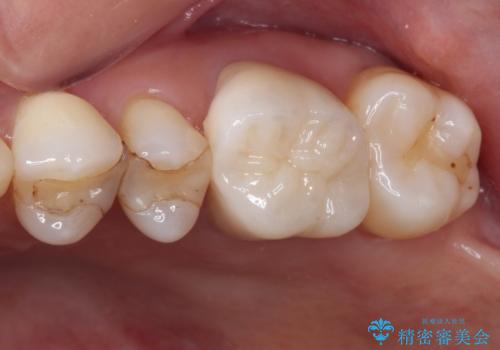

- 他院で矯正治療を行った後、保険診療で装着した前歯のクラウンの変色を気にして来院された患者様です。

保険診療では樹脂を用いた素材で製作するため、水分が吸収されやすく、一緒に色素が取り込まれるために変色をしてしまいます。

また、裏打ちに主に銀を用いた金属材料を使用するため、金属自体が黒くなったり、イオンとなり溶け出したりして、歯肉ラインが黒くなってしまうことがあります。

一部は根管治療を行い、土台の金属も歯の色に近いものへと変更した上で、オールセラミッククラウンにて補綴することとしました。